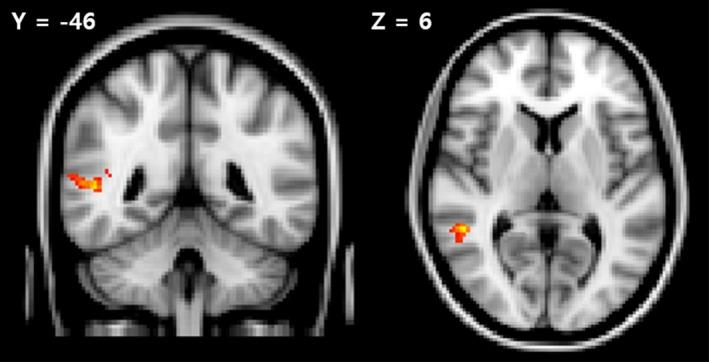

The patients with schizophrenia exhibited decreased discriminability and increased activation of the right superior temporal gyrus compared with the controls during correct responses. Furthermore, aberrant network activities were found in the frontopolar and language comprehension networks in the patients.